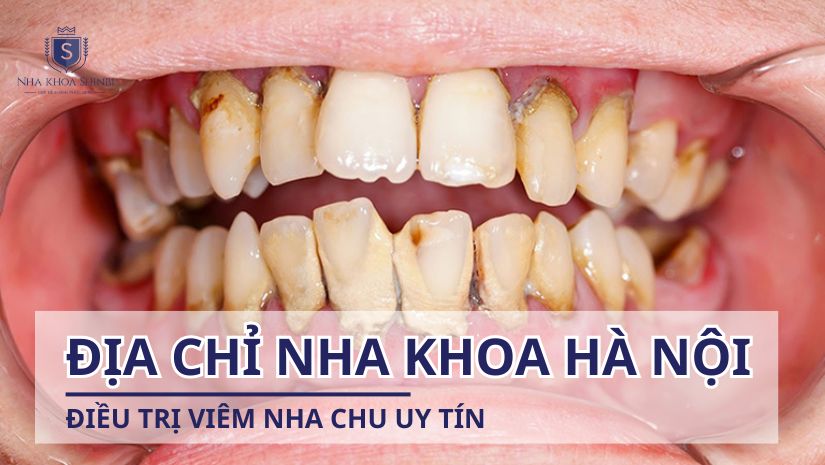

Bạn đang tìm địa chỉ chữa viêm nha chu cho người lớn tuổi tại Hà Nội? Viêm nha chu là bệnh phổ biến và gây nhiều phiền toái, đặc biệt với người già. Đừng lo, trong bài viết này mình sẽ chia sẻ những nha khoa uy tín, có dịch vụ chuyên biệt giúp điều trị hiệu quả, an toàn cho người lớn tuổi. Cùng tìm hiểu nhé!

Nha khoa Shinbi – Địa chỉ nha khoa điều trị viêm nha chu uy tín cho người lớn tuổi tại Hà Nội

Nếu bạn đang tìm kiếm địa chỉ chữa viêm nha chu cho người lớn tuổi tại Hà Nội uy tín, thì Nha khoa Shinbi là một cái tên đáng cân nhắc. Shinbi Dental không chỉ chú trọng đến điều trị mà còn quan tâm đến trải nghiệm chăm sóc đặc biệt cho người cao tuổi.

Tại cơ sở Hà Nội, Nha khoa Shinbi cung cấp dịch vụ “Thăm khám và phẫu thuật nha chu”, bao gồm các vấn đề từ nhẹ đến nặng về viêm nướu, tụt lợi và tiêu xương quanh răng. Đây là lựa chọn lý tưởng cho người lớn tuổi, người thường gặp nhiều vấn đề răng miệng do tuổi tác và sức đề kháng yếu.